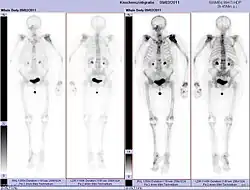

Ganzkörperknochenszintigramm mit 99mTc-HDP der Patientin mit der Oberarmfraktur aufgrund einer Brustkrebsmetastase

Skelettszintigrafie

Die Skelettszintigrafie ist derzeit noch der Goldstandard für das Erkennen von Knochenmetastasen. Das Verfahren ist relativ aufwändig, kostenintensiv und unterliegt einigen diagnostischen Limitationen.[88] Im Gegensatz zur Röntgendiagnostik kann bei der Skelettszintigrafie relativ einfach der gesamte Befall des Skeletts dargestellt werden.[85] Eine Skelettszintigrafie ist für das Aufspüren von Knochenmetastasen normalerweise deutlich empfindlicher als eine Röntgenaufnahme. Die Sensitivität der Skelettszintigraphie ist mit 95 % recht hoch. Im Durchschnitt werden mit dieser Methode Knochenmetastasen sechs Monate vor ihrer Erkennung im Röntgenbild nachgewiesen.[111] Dagegen ist die Spezifität wesentlich geringer,[112] da nahezu alle tumorösen und inflammatorischen Veränderungen am Skelett zu einer Anreicherung des Radiotracers in diesen Arealen führt. Der erhöhte Knochenumsatz und Reparaturvorgänge im Randbereich von osteolytischen Knochenmetastasen hat eine erhöhte Speicherung des Radiotracers zur Folge, die als Hot Spot im Szintigramm sichtbar sind.[113] Bei Knochenmetastasen von Lungen- oder Brustkrebs kann die reaktive Knochenneubildung in seltenen Fällen ausbleiben.[114] Im Szintigramm ist dies dann als Cold Spot, ein Bereich mit reduzierter Nuklidaufnahme, zu erkennen.[115]

Beim rein osteolytischen multiplen Myelom sind bei der Skelettszintigrafie dagegen keine Veränderungen zu erkennen.[85] Während im Röntgenbild das Ergebnis der Aufsummierung von Stoffwechselvorgängen am Knochen über einen längeren Zeitpunkt zu sehen ist, stellt die Skelettszintigrafie eine Momentaufnahme der aktuellen Stoffwechselvorgänge an den Knochen dar. Deshalb können beispielsweise Knochenmetastasen mit osteoplastischen Prozessen, die mit einer sehr niedrigen Stoffwechselrate ablaufen, im Szintigramm unauffällig bleiben.[116]

Die Skelettszintigrafie wird vor allem zur Therapiekontrolle der Chemo-, Strahlen- oder Radionuklidtherapie, für die Stadienbestimmung (engl. staging) beim CUP-Syndrom angewendet und zur Nachsorge bei Krebserkrankungen eingesetzt.[85]

Knochenmetastasen unterschiedlicher Tumorerkrankungen können mit PET/CT sehr gut nachgewiesen werden. Das Verfahren ist sensitiver als die SPECT und erheblich sensitiver als die Skelettszintigrafie, jedoch auch aufwändiger und somit teurer. Je nach Tumorentität werden unterschiedliche Tracer verwendet, meist jedoch FDG und Natriumfluorid, beim Prostata-Krebs auch 18F-Cholin. Metabolische Aktivität des Tumors ist mit Hilfe des Tracers FDG, die Reaktion des Knochens auf den Tumor mit der Natriumfluorid-PET/CT meist gut darstellbar.[121]